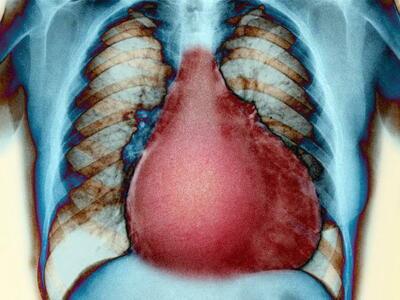

Кардиомегалия

Кардиомегалия – заболевание, сопровождающееся увеличением размеров и массы человеческого сердца. По-другому болезнь называют синдромом "бычьего сердца" (из-за больших ключевых параметров миокарда).

- рентгенография грудной клетки;